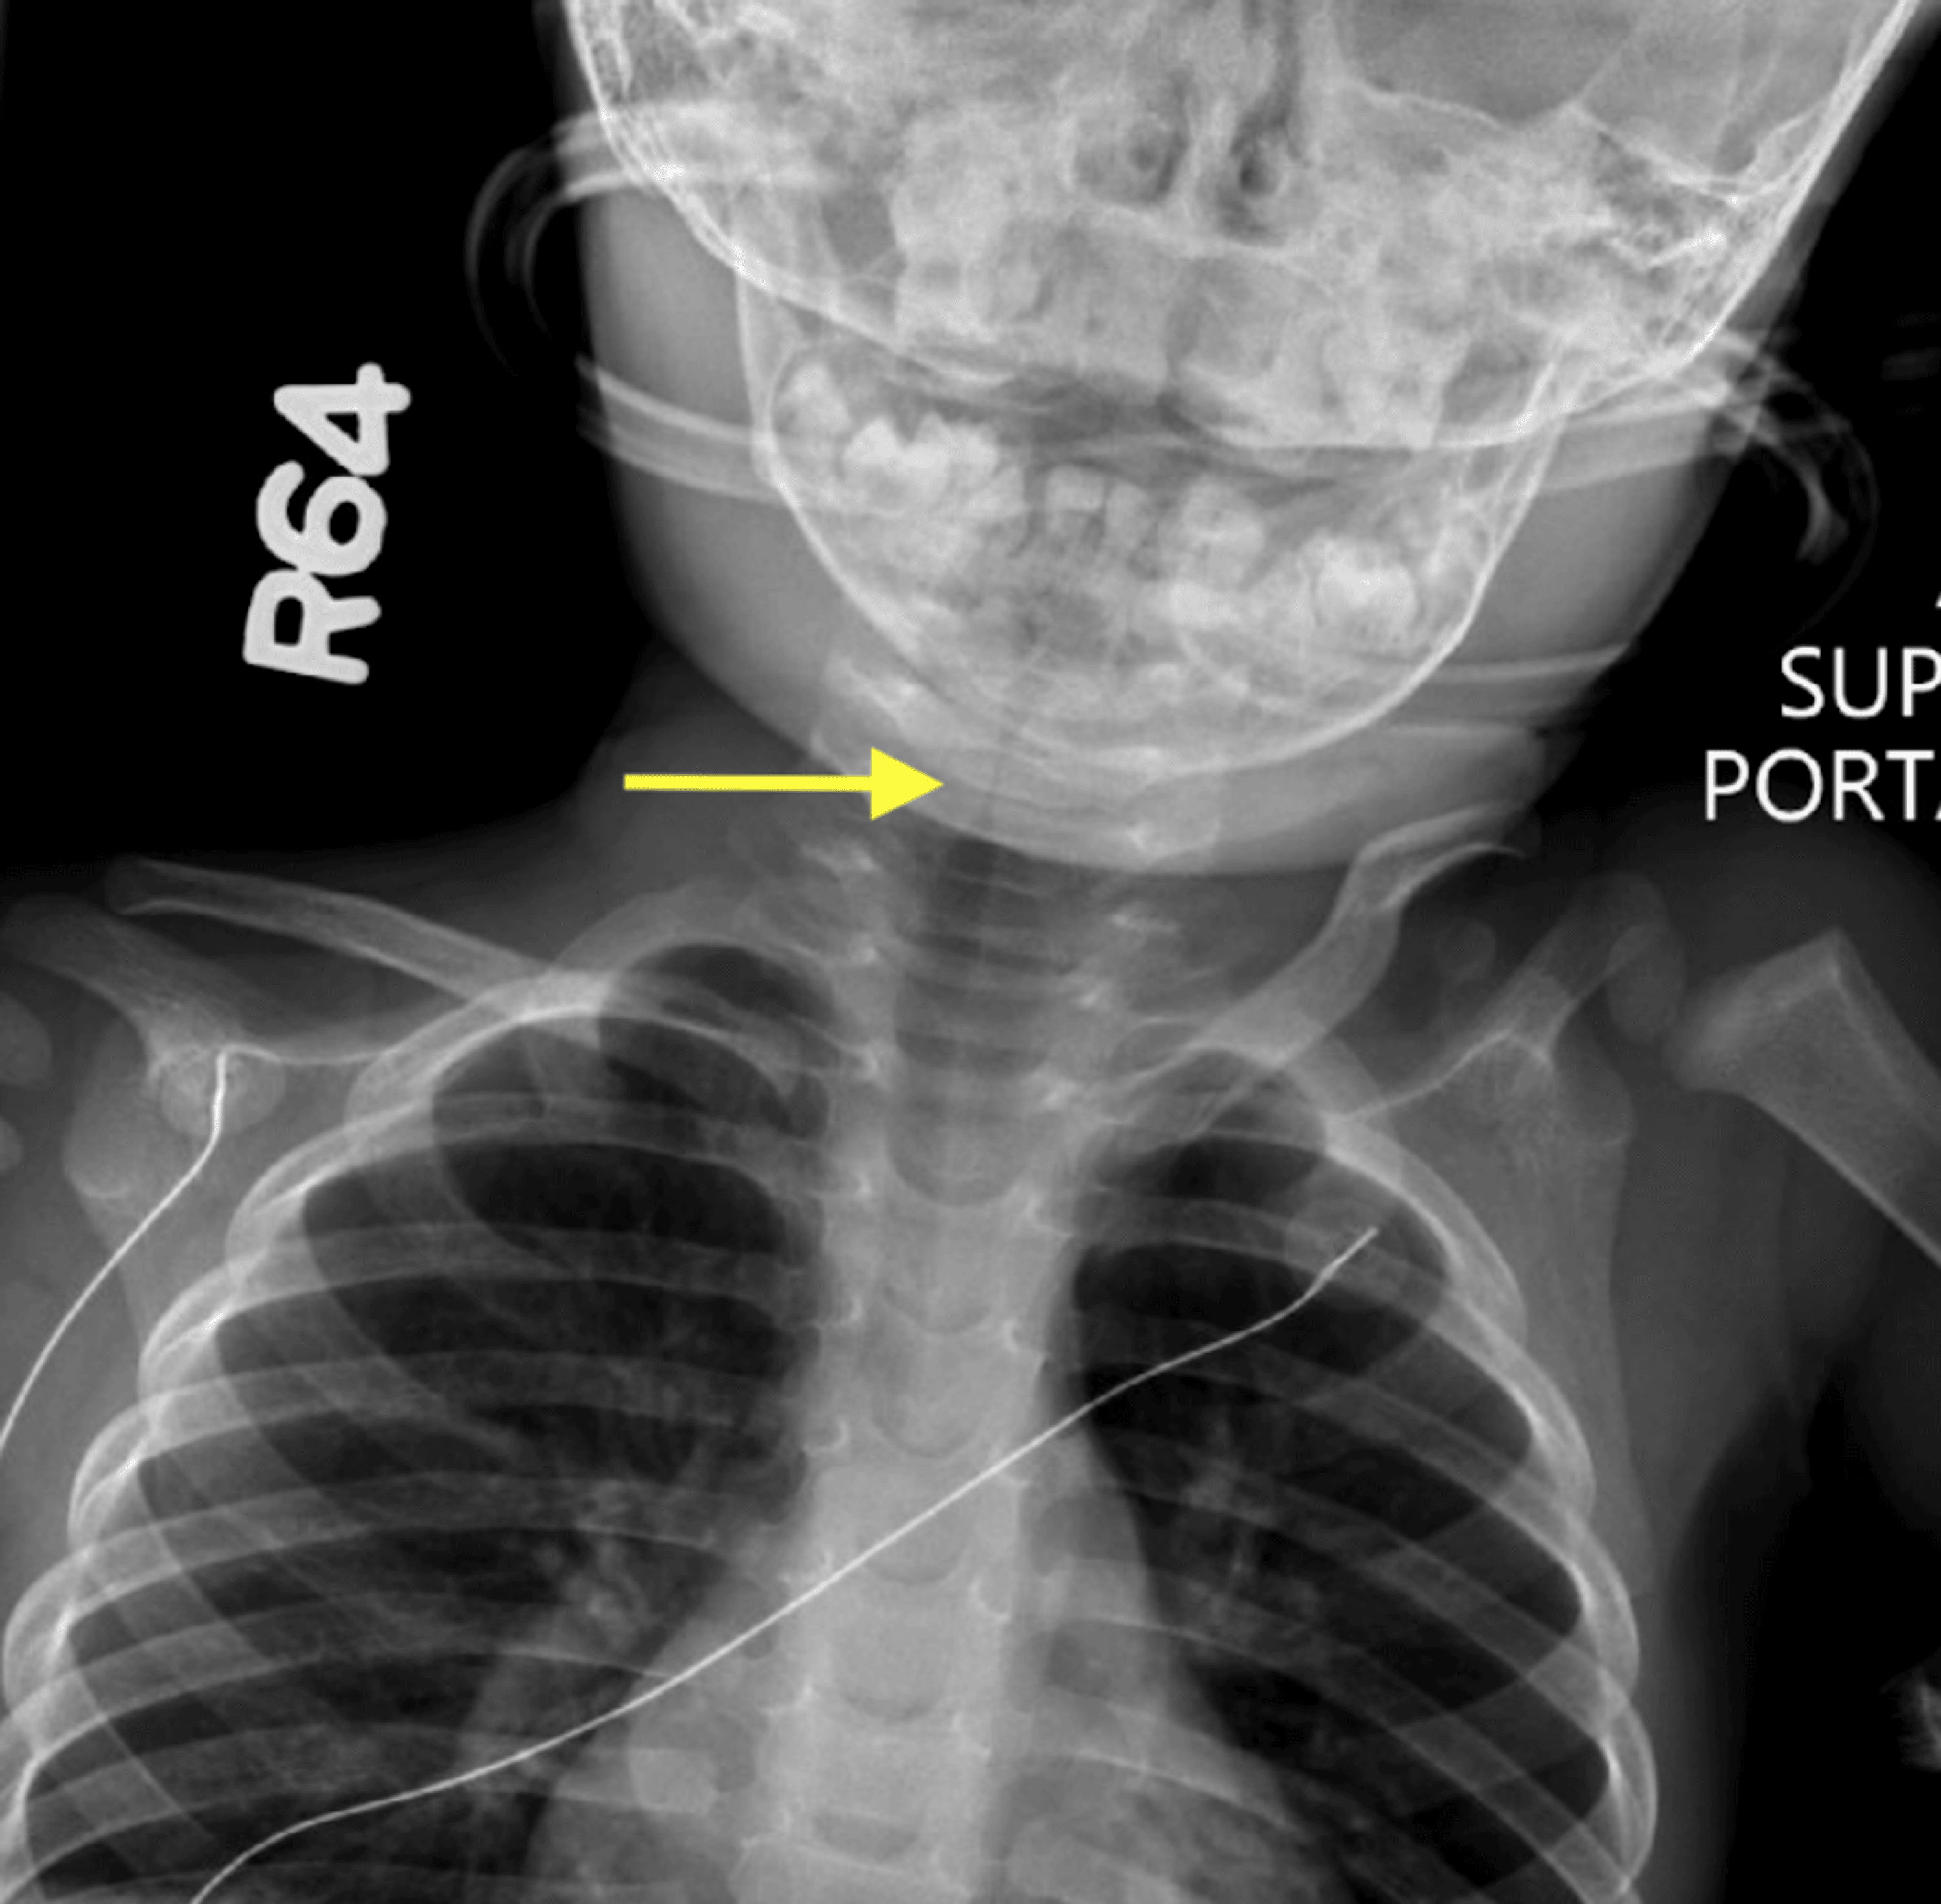

Radiological imaging of the subglottic tracheal stenosis in frontal (A Tracheal Subglottic Stenosis Learn about tracheal stenosis, a condition that narrows your windpipe and makes breathing difficult. Subglottic and tracheal stenosis can occur due to prolonged intubation, surgical procedures, autoimmune or inflammatory disorders, infections, and gerd. Subglottic stenosis and tracheal stenosis (ts) are broad terms that describe a stricture or narrowing of the subglottic and. This study describes the characteristics and prognosis of. Tracheal Subglottic Stenosis.

Cureus Recurrent Subglottic Stenosis in a 16MonthOld Male in the

Cureus Recurrent Subglottic Stenosis in a 16MonthOld Male in the Tracheal Subglottic Stenosis Subglottic and tracheal stenosis can occur due to prolonged intubation, surgical procedures, autoimmune or inflammatory disorders, infections, and gerd. Subglottic stenosis and tracheal stenosis (ts) are broad terms that describe a stricture or narrowing of the subglottic and. Tracheal and subglottic stenosis occur with a narrowing of your windpipe, which is the most critical conduit of air travel from your. Tracheal Subglottic Stenosis.